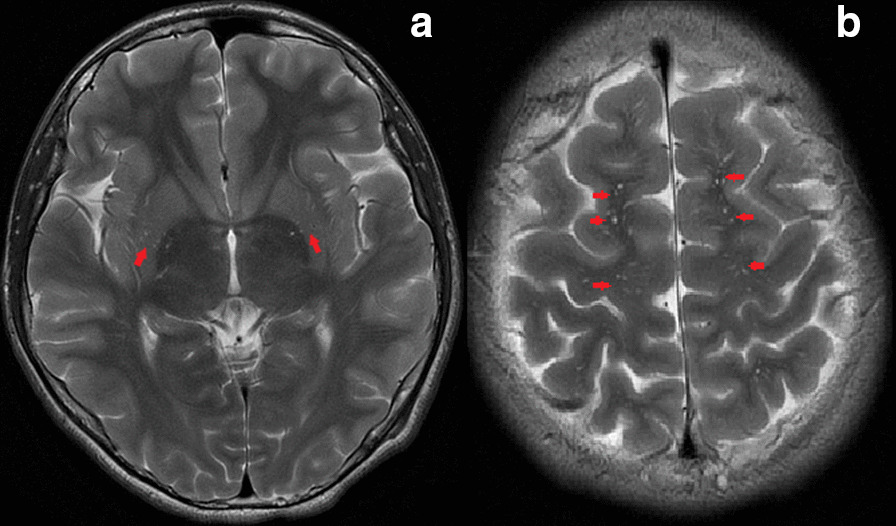

When the proband was referred to our hospital, the family history established that she had a 15-year-old brother attending junior middle school. Apart from obvious gait abnormality and poor school sports performance evident from 13 years of age, his past history was unremarkable. He developed gait paraparesis with slowly progressive aggravation, but without intellectual or psychological problems. Neurological examination revealed hyper-reflexia and spasticity of the lower limbs, which indicated the upper motor neuron damage. His liver function markers, serum lipids, coagulation function and whole blood cell counts were all found to be normal. Brain magnetic resonance imaging (MRI) showed hyperintensity in the bilateral basal ganglia and white matter of frontal parietal on T2-weighted imaging (T2WI) which was considered as the perivascular spaces enlarged (Fig. 4). According to the clinical manifestation, physical examinations and image results, diagnosis of the pure SPG5 was suspected. The CYP7B1 mutations identified in the proband were verified in him, and in the parents by Sanger sequencing. Compound heterozygous mutations were identified in him, and both parents were found to be heterozygous for each mutation, consistent with the autosomal recessive nature of bile acid synthesis disorders. He was then diagnosed as SPG5 and chose to be treated with CDCA (6 mg/kg/day), the same treatment used for his sister, and began rehabilitation training at the specialized physiotherapy department. After commence of the treatment, his gait abnormality and poor school sports performance did not improve. He still tripped a lot, and one time he fell on the ground and needed aid from his schoolmates to stand up. In follow up, he was reported by the parents to be non-compliant to CDCA therapy and this treatment was terminated after 2 months.

Fig. 4.

Magnetic resonance imaging (MRI) data obtained from the brother with CYP7B1 deficiency, T2-weighted images show massively enlarged perivascular spaces (showed by red arrows) in the bilateral basal ganglia (a) and white matter of frontal parietal (b)